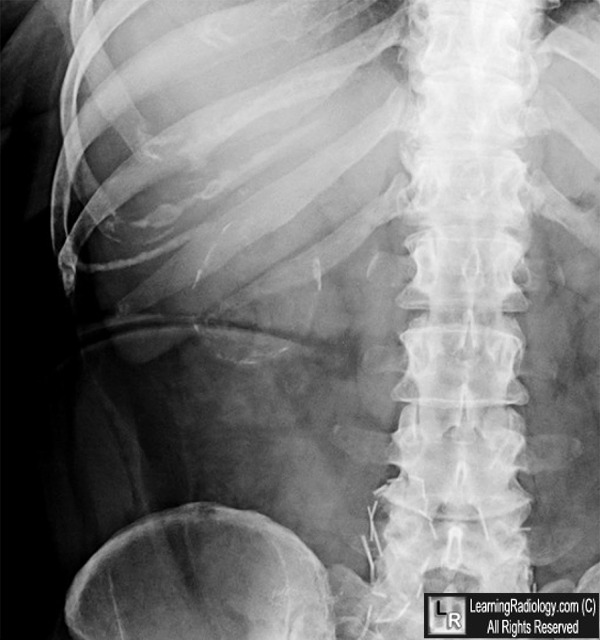

Porcelain Gallbladder. Upper: Radiograph of right upper quadrant of the abdomen shows a curvilinear calcification

indicating calcification if the wall of a "hollow viscous" in the region of the gallbladder (white arrows).

Lower: Axial CT image of the upper abdomen in the same patient confirms the thin calcification in the gallbladder wall (yellow arrows).

- On conventional radiographs or CT, curvilinear calcifications in segment of the wall or entire wall

- Thickness of calcification may vary